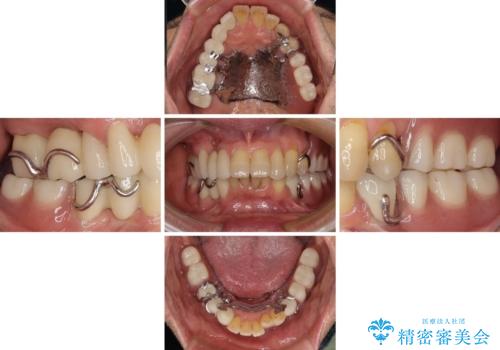

- 以前入れ歯を製作したものの、装着感が悪く使用できなかったとのことで来院された患者様です。

インプラントによる治療プランも提案しましたが、インプラントは避けたいとのご希望であったため、入れ歯による補綴治療を行うこととしました。

自費治療の義歯は装着感がとても良いですが、急に入れ歯を装着すると、異物感が強く継続使用できなくなるため、仮歯の期間中に保険治療での義歯を装着してもらい、口腔内を義歯に慣れさせるようにしました。

より適合の良い義歯とするため、セラミッククラウンなどは義歯の設計に合わせた土台の歯となるよう全て再製作をし、安定感に優れた義歯を製作することができました。